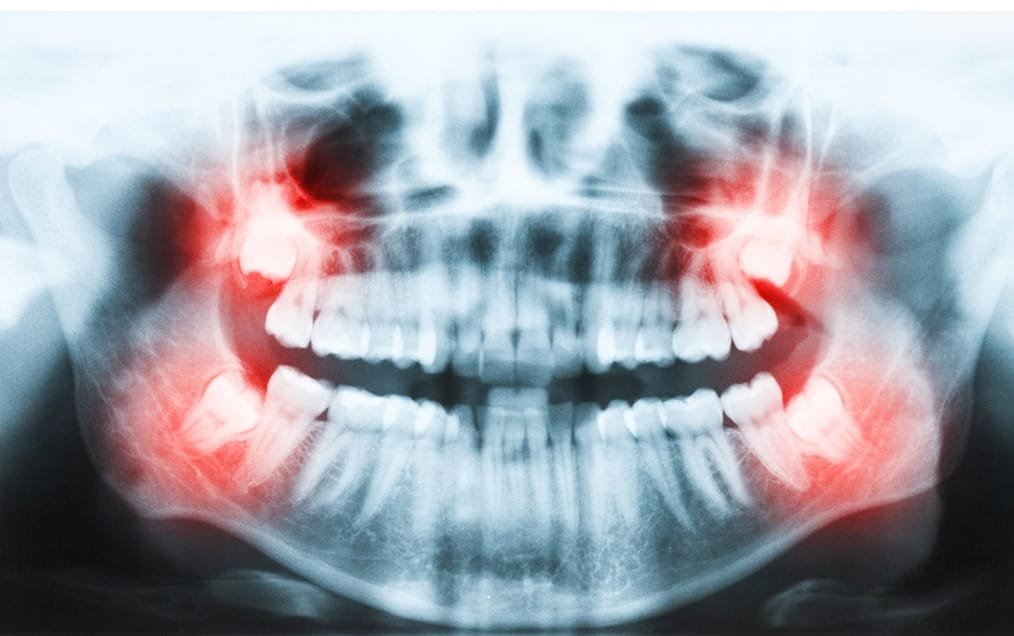

Wisdom teeth are the last set of molars to emerge and are located in the very back part of the mouth. They generally come in between the ages of 14-30, although some people never get them at all. For many people, wisdom teeth come in properly and cause no problems at all. For some people, however, problems arise, and intervention is necessary to avoid future complications. If left untreated, problematic wisdom teeth can lead to pain, tooth decay, gum disease, and occlusion (bite) problems.

Wisdom teeth can be a source of concern for many people. If there is not enough room in the back of the mouth for wisdom teeth to erupt properly, their growth can be disrupted. For some people, wisdom teeth erupt only partially through the gums, which can result in crowding issues with the surrounding teeth, cavities, gum infections and/or severe pain. Sometimes wisdom teeth can grow in unusual directions, which can cause complications like crowding and damage to adjacent second molars. Impacted wisdom teeth occur when there is not enough room for them to erupt in the mouth and they become stuck under the gums, unable to emerge. When wisdom teeth are impacted in the jaw, this can provide a very fertile ground for bacteria to grow at the opening of the mouth, which can lead to gum infection which could cause considerable discomfort, pain, swelling, and illness. Oftentimes your dentist can foresee future concerns with your situation and may recommend the removal of your wisdom teeth.